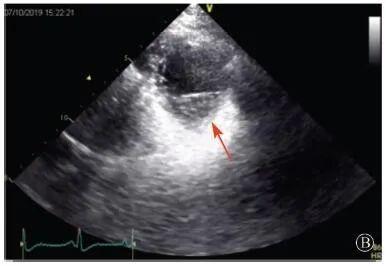

患者入院后無特殊不適,心率70次/min,血壓110/60 mmHg,心功能Ⅱ級。查血常規(guī):血紅蛋白139 g/L,白細胞7.39×109/L,血小板221×109/L。尿常規(guī)、便常規(guī)+潛血均正常。生化:丙氨酸氨基轉移酶38 U/L,白蛋白47 g/L,鉀3.9 mmol/L,肌酐(酶法)65 μmol/L,總膽固醇3.52 mmol/L,低密度脂蛋白膽固醇2.08 mmol/L。CK:1256→487 U/L,CK-MB 9.7→3.8 μg/L,cTnI 85.90→68.50 pg/ml。N末端B型利鈉肽原70 pg/ml。CK同工酶電泳:肌酸激酶MM質量100.0%(此時CK-MB已正常)。血沉1 mm/第1小時,高敏C反應蛋白1.61 mg/L;補體:C3 0.876 g/L,C4 0.174 g/L。免疫球蛋白:IgG 9.52 g/L,IgA 1.73 g/L,IgM 0.62 g/L。血清蛋白電泳未見M蛋白。糖化血紅蛋白5.1%。乳酸(運動前)1.1 mmol/L,乳酸(運動中)6.6 mmol/L,乳酸(運動后)7.8 mmol/L。肌炎抗體譜:抗PM-SCL75(+),余均(-)。心電圖:aVL、V5、V6導聯(lián)T波倒置(圖2)。冠狀動脈CT未見明顯異常。超聲心動圖:左室舒張末內(nèi)徑55 mm,左室收縮功能減低,心尖部、左室壁普遍運動減低,以左室下后壁為著,左室下后壁肌小梁明顯增多可見隱窩,疏松層與致密層之比為1.7;左室射血分數(shù)(雙平面)45%;右冠狀動脈開口6.5 mm,開口處未見明確瘤樣擴張(圖3)。

B:胸骨旁左室短軸切面心尖水平,可見心肌肌小梁增多,其內(nèi)可見隱窩(箭頭所示)

圖3 患者入院后超聲心動圖